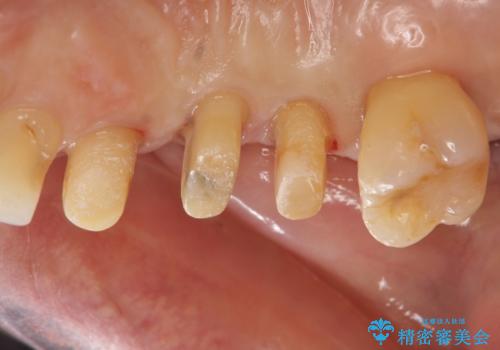

検査の結果、強い歯ぎしりによる歯の周囲の骨の吸収が認められたため歯槽骨の再生・歯周ポケットの除去・力に対抗する連結補綴・補綴前処置としての小矯正を計画します。

今回連結補綴を行うにあたり、歯周病の問題を解決するために再生療法・歯周ポケット除去手術を、またより歯の神経を保存し力に対抗できる環境を整えるために小矯正を行い精度の高いメタルボンドクラウンを製作することができました。